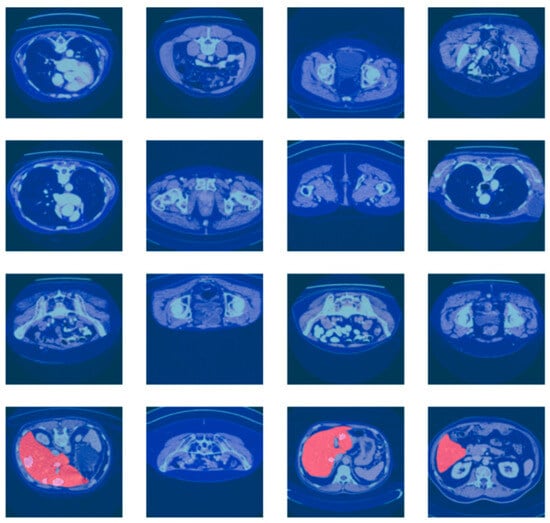

For more reliable experimental assessment, the merged dataset (LiTS17 + Radiopaedia) was split at the patient level (i.e., to prevent data leakage between splits) into train, validation, and test sets at a ratio of 70:10:20, ensuring that CT scans from the same patient were present in at most one of the splits. The large class imbalance between tumor and non-tumor regions was addressed by using a weighted loss function and balanced patch sampling at training time. While the current work reports results for a single fixed split, several training courses run with different random seeds were performed in the reported experiments to verify the stability of the results. These are the CT scan images with associated liver segmentation masks in Figure 5. Each of the images is preprocessed to focus on the liver region. The masks are used to indicate the location of the liver in the CT scan. The batch of images and masks shows the preprocessing and segmentation.

Figure 5.

Batch of CT scan images with liver segmentation masks.